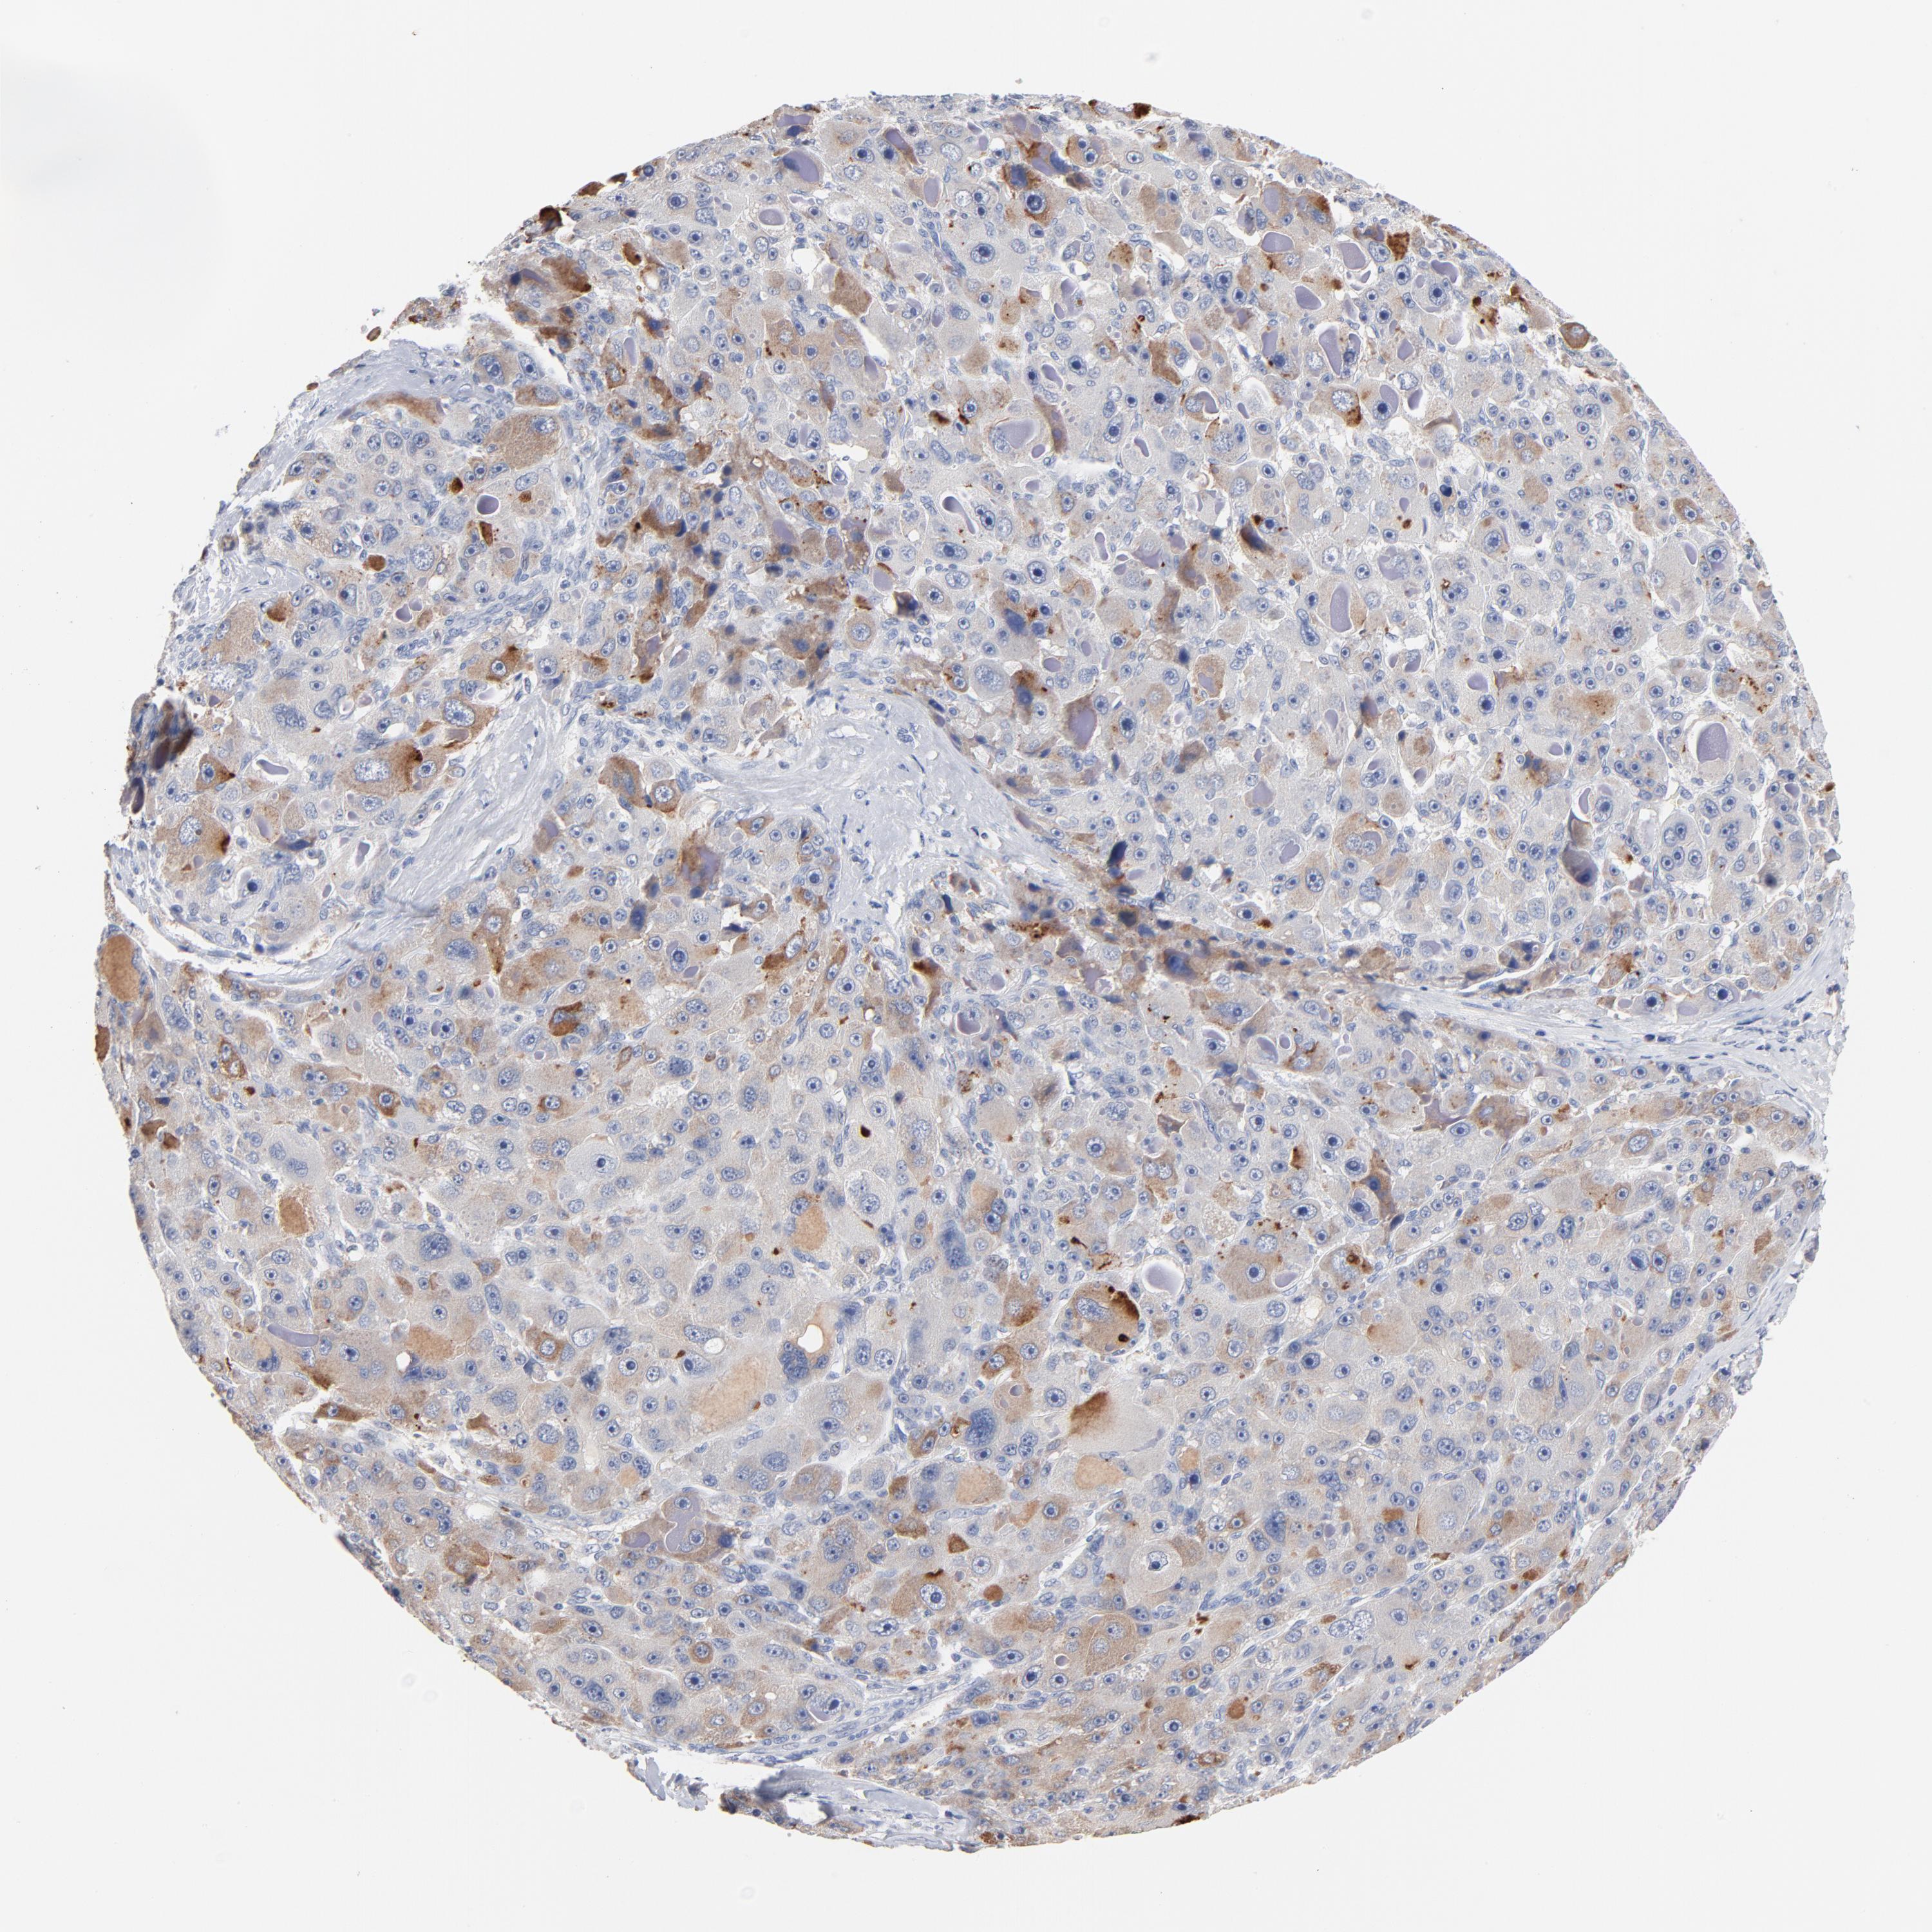

LIVER CANCER - Protein expressioni

A mouse-over function shows sample information and annotation data. Click on an image to view it in a full screen mode. Samples can be filtered based on level of antibody staining by selecting one or several of the following categories: high, medium, low and not detected. The assay and annotation is described here.

Note that samples used for immunohistochemistry by the Human Protein Atlas do not correspond to samples in the TCGA dataset.

Antibody stainingi

Antibody staining in the annotated cell types in the current human tissue is reported as not detected, low, medium, or high, based on conventional immunohistochemistry profiling in selected tissues. This score is based on the combination of the staining intensity and fraction of stained cells.

Each image is clickable and will lead to virtual microscopy that enables deeper exploration of all samples and also displays staining intensity scores, fraction scores and subcellular localization as well as patient and tissue information for each sample.

Antibody HPA003607

Staining

High

Medium

Low

Not detected

Intensity

Strong

Moderate

Weak

Negative

Quantity

>75%

75%-25%

<25%

None

Location

Nuclear

Cytoplasmic/membranous

Cytoplasmic/membranous,nuclear

Cholangiocarcinoma

Carcinoma, Hepatocellular, NOS